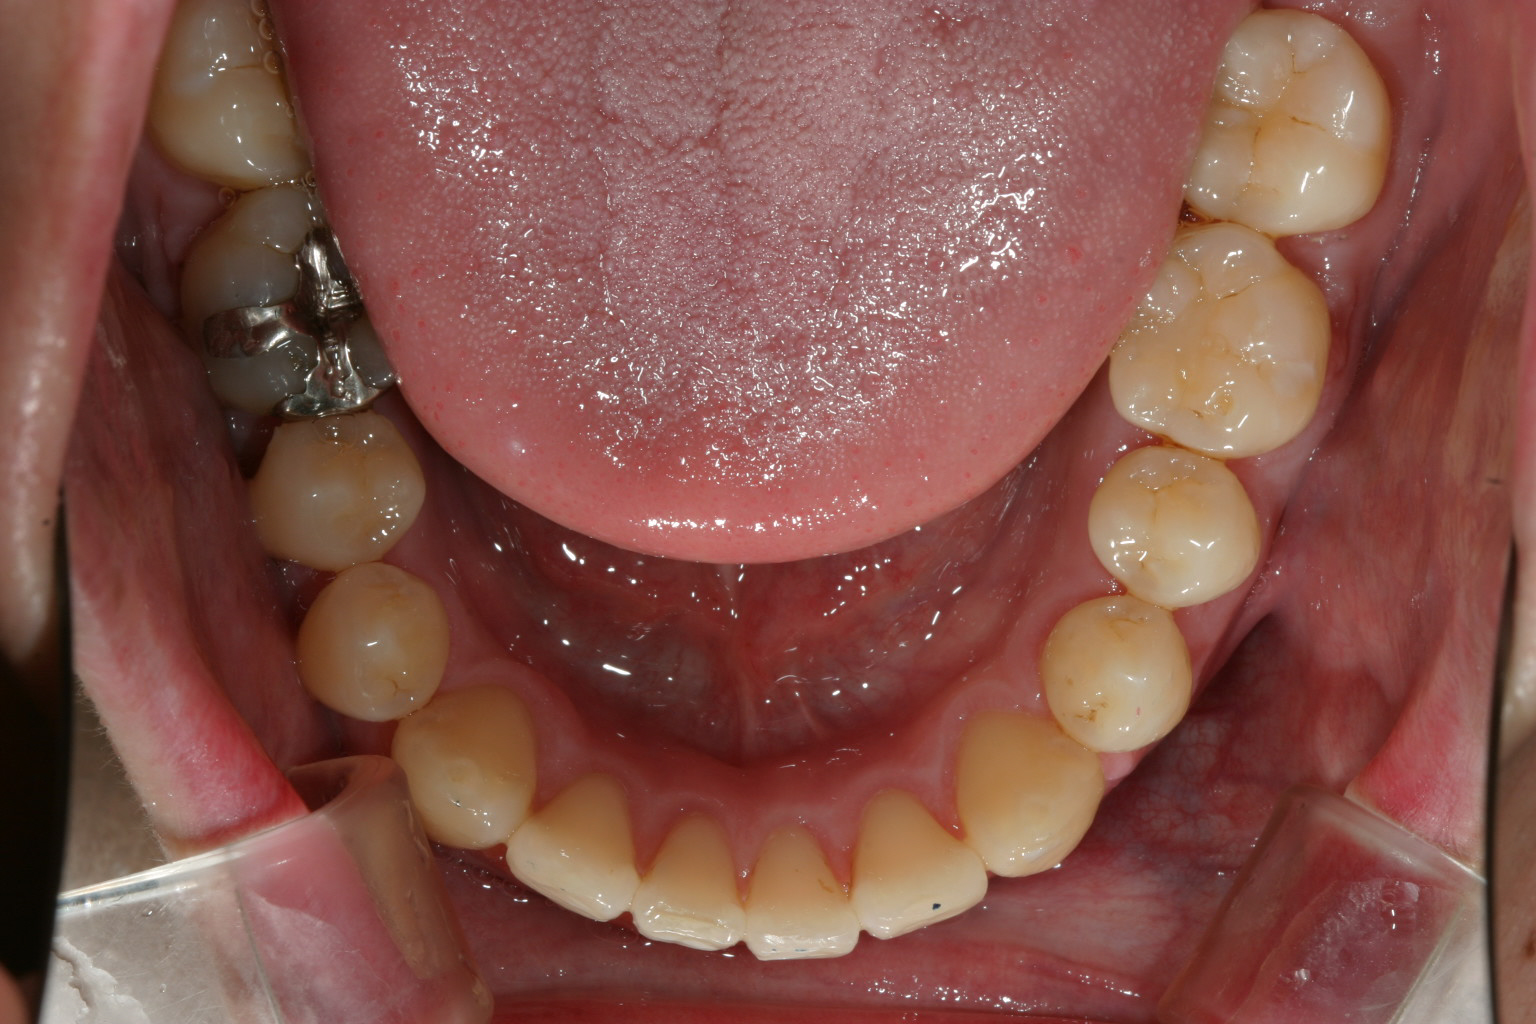

11か月後です。 綺麗なアーチに改善しました。

下顎のアーチも広がり綺麗になりました。